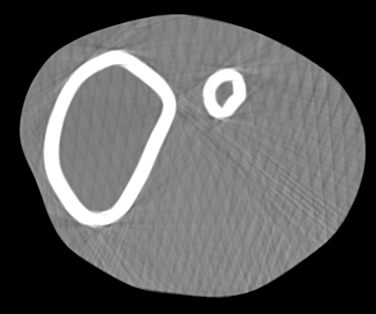

Involuntary subject motion is the main source of artifacts in weight-bearing cone-beam CT of the knee. To achieve image quality for clinical diagnosis, the motion needs to be compensated. We propose to use inertial measurement units (IMUs) attached to the leg for motion estimation. We perform a simulation study using real motion recorded with an optical tracking system. Three IMU-based correction approaches are evaluated, namely rigid motion correction, non-rigid 2D projection deformation and non-rigid 3D dynamic reconstruction. We present an initialization process based on the system geometry. With an IMU noise simulation, we investigate the applicability of the proposed methods in real applications. All proposed IMU-based approaches correct motion at least as good as a state-of-the-art marker-based approach. The structural similarity index and the root mean squared error between motion-free and motion corrected volumes are improved by 24-35% and 78-85%, respectively, compared with the uncorrected case. The noise analysis shows that the noise levels of commercially available IMUs need to be improved by a factor of $10^5$ which is currently only achieved by specialized hardware not robust enough for the application. The presented study confirms the feasibility of this novel approach and defines improvements necessary for a real application.